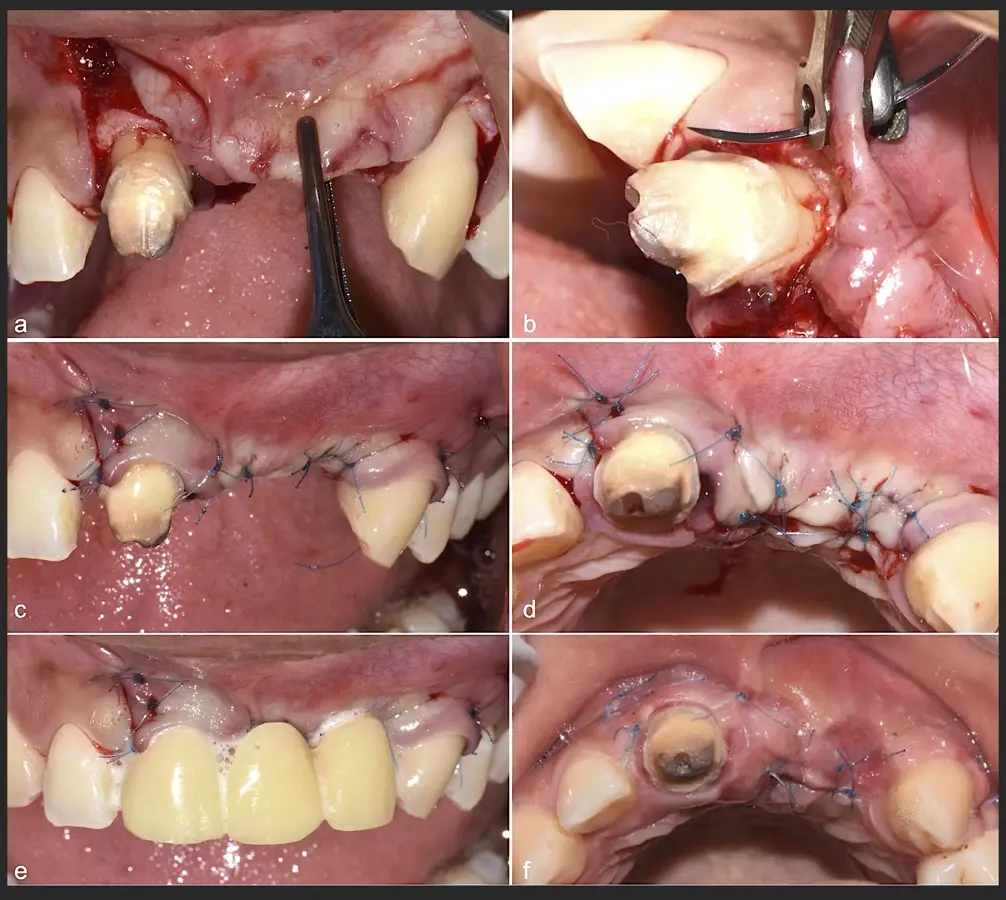

Paciente de sexo femenino de 36 años de edad, llega a la consulta por presentar una restauración protésica inadecuada. En el examen clínico se observa una restauración protésica provisional acrílica sobre las piezas 1.1 y 2.2. Adicionalmente, se aprecia recesión gingival a nivel de la pieza 2.2 y deficiencia horizontal severa de reborde a nivel de la zona edéntula correspondiente a la pieza 2.1. En la evaluación tomográfica se observa ausencia total de tabla ósea vestibular en la pieza 2.2, y se corrobora el déficit en la zona edéntula de la pieza 2.1, para lo cual se indica una reconstrucción de estructuras óseas con hueso en bloque de origen bovino y posteriormente la colocación de implantes dentales.

Figura 35. Decolado a espesor total sobrepasando la línea mucogingival (a, b).

Figura 45. Afrontamiento de colgajo y sutura (a - e). Control a los 7 días postquirúrgico (f).